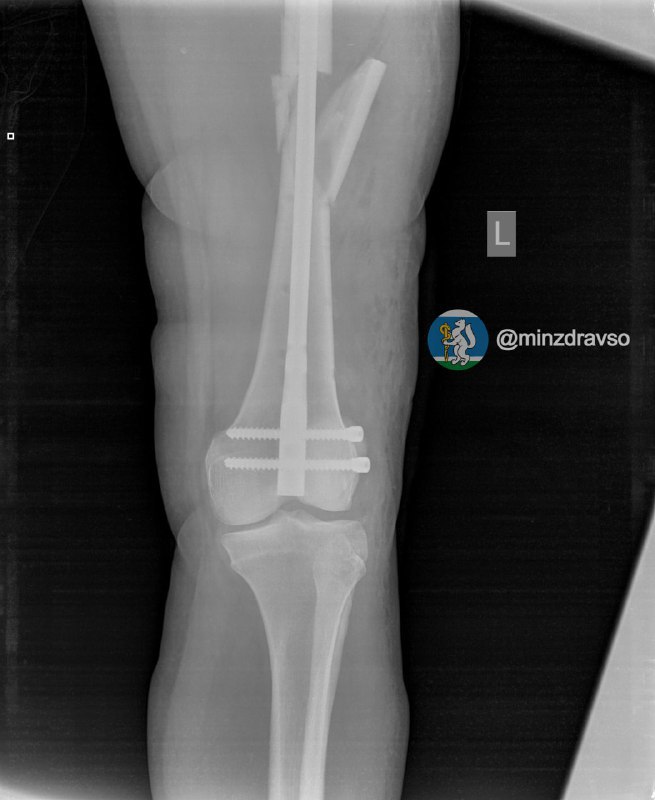

У нее диагностировали ушиб головы и сложный оскольчатый перелом левой бедренной кости.

Первую операцию свердловчанке провели экстренно в условиях шоковой операционной приёмного отделения.Через неделю, когда состояние женщины стабилизировалось, врачи смогли приступили к операции по замене аппаратов внешней фиксации на внутренний фиксатор. Ей был проведён блокирующий интрамедуллярный остеосинтез.